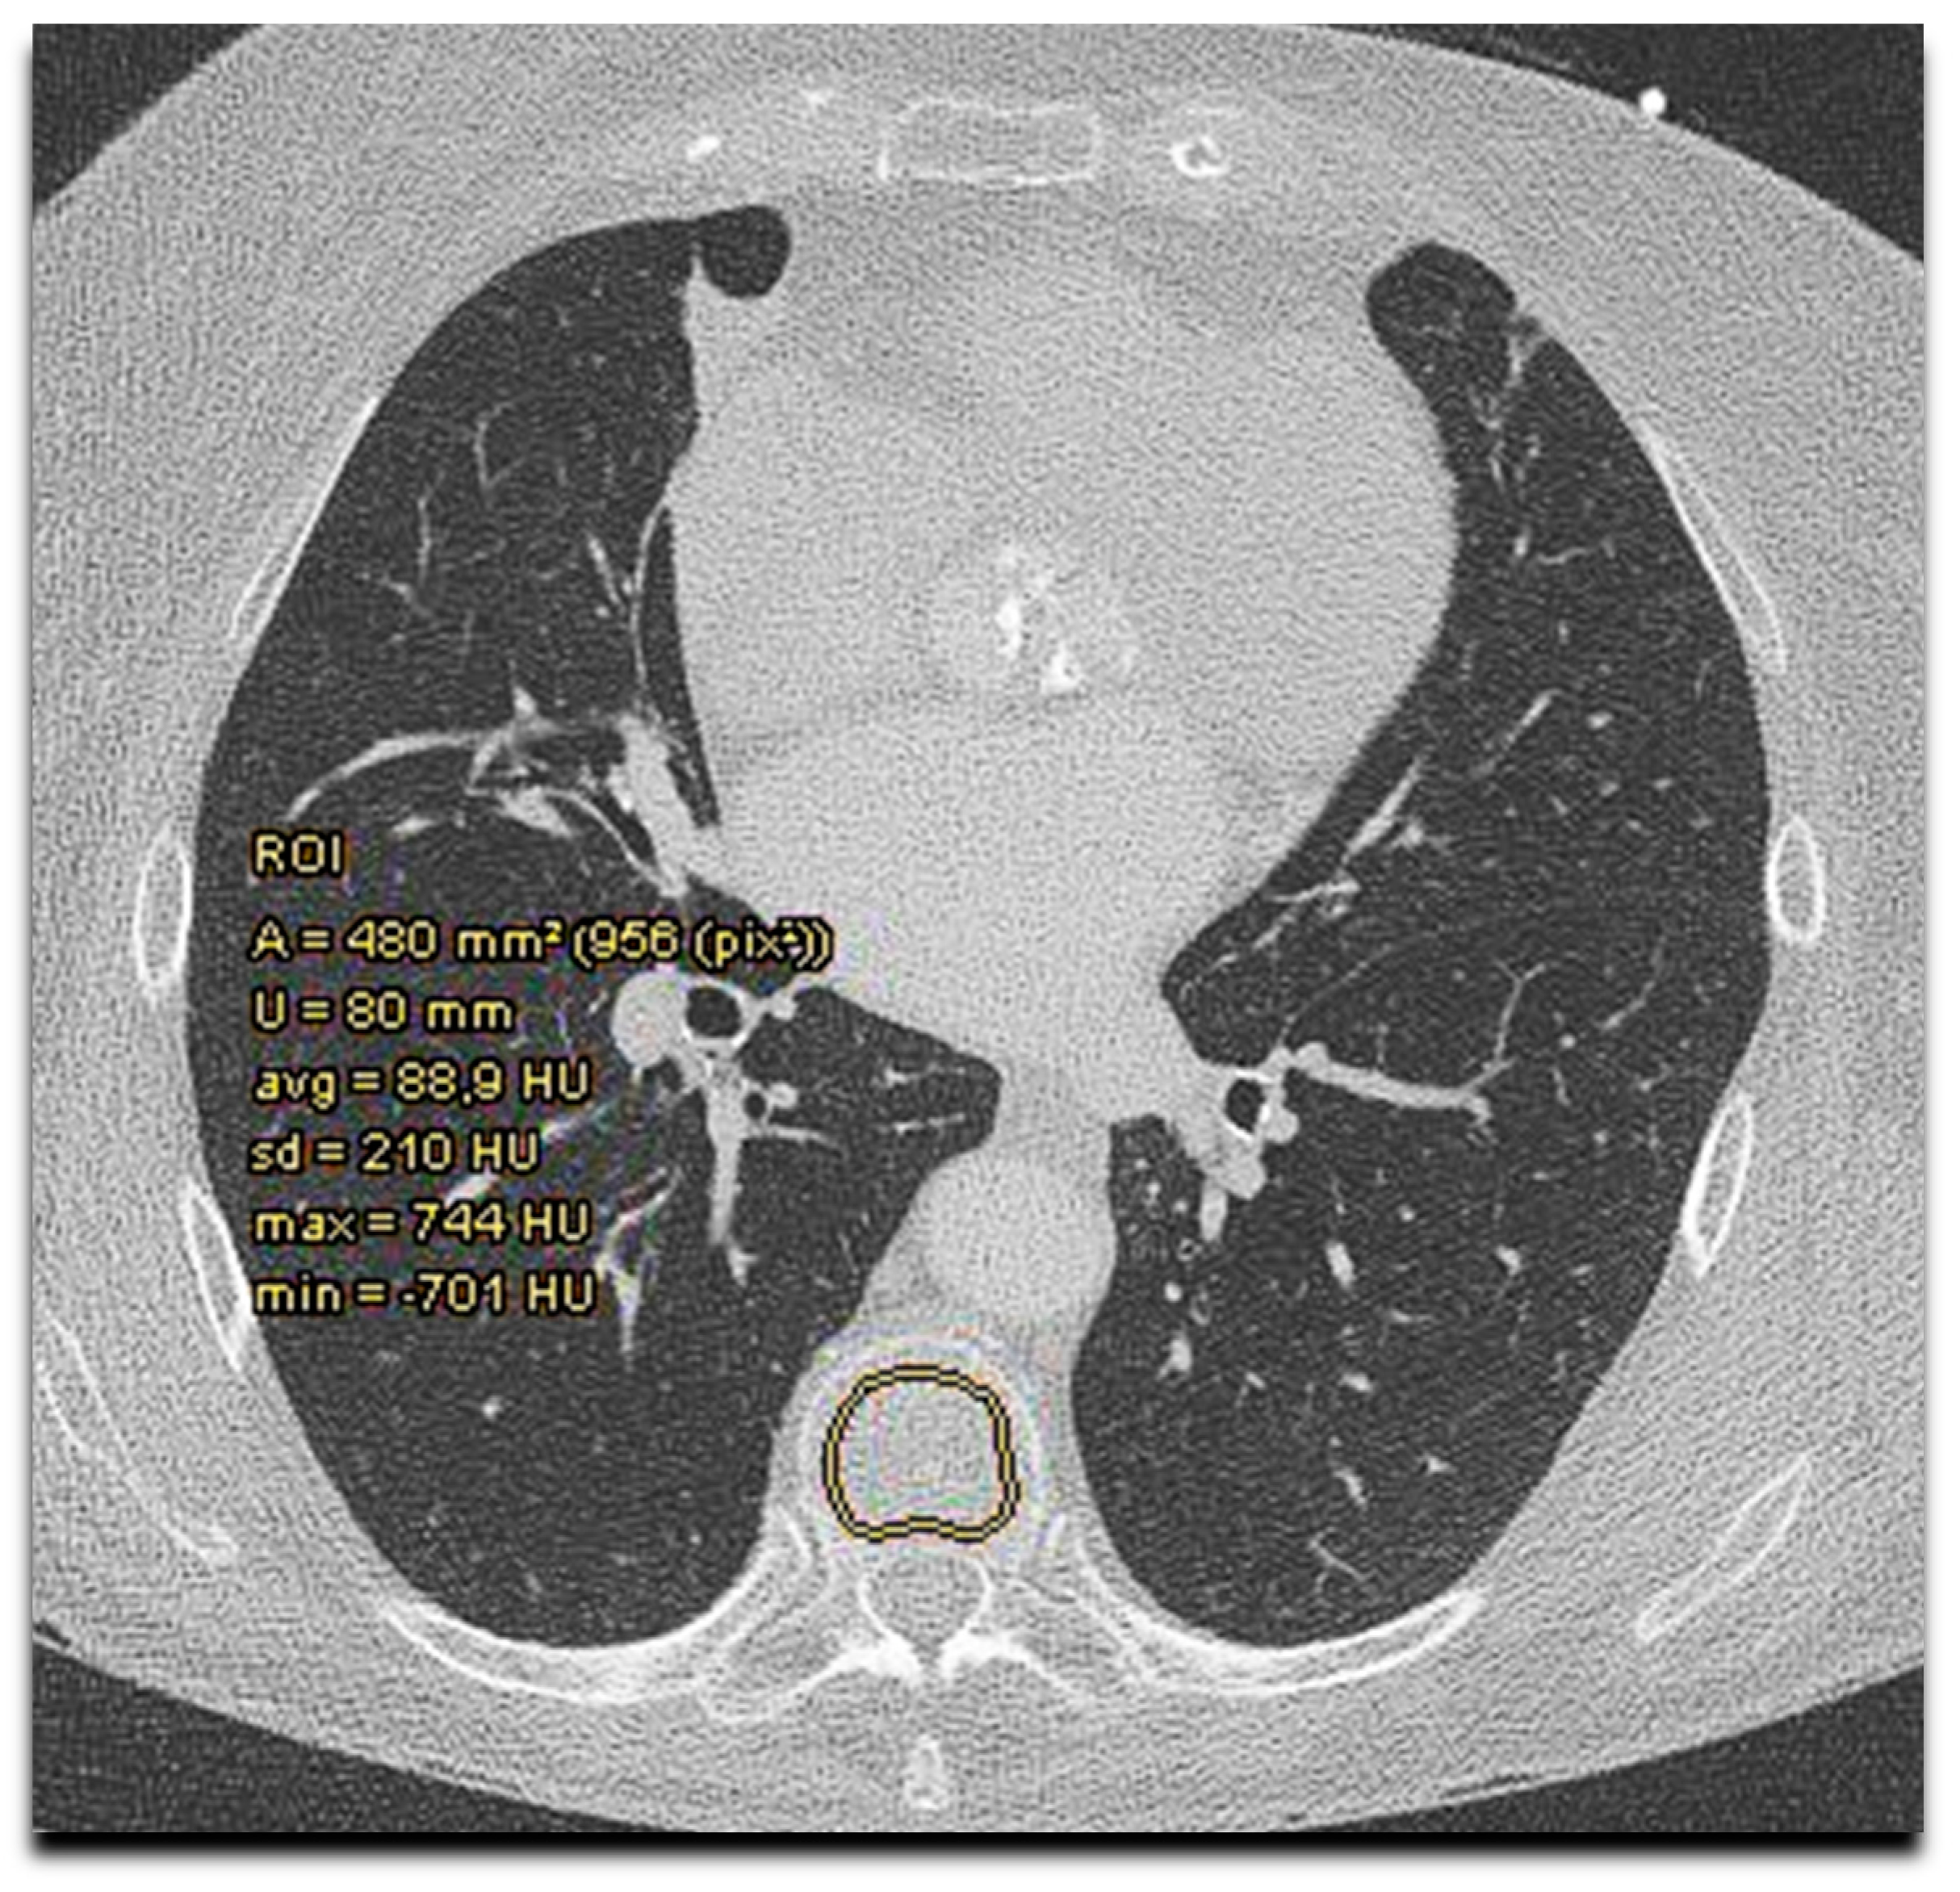

2.4. CT Assessment

| CT bone density | ||||

| Average HU in thoracal vertebra | 147.5 (75.4) | 120.0 (44.8) | 255.8 (73.8) | <0.001 |